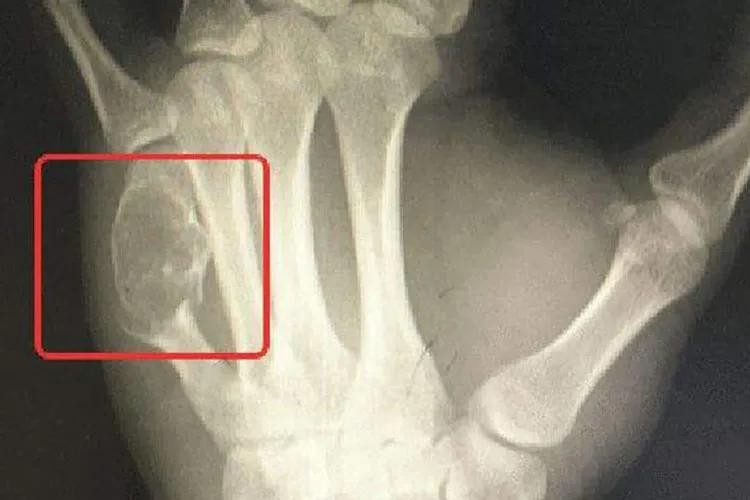

骨癌的早期症状图片

许多骨癌早期并没有典型的症状表现,少数骨癌的早期可出现疼痛症状,开始为间歇性,后来发展为持续性,夜间较明显,晚期疼痛加重。有的病人因疼痛剧烈而抱肤辗转,彻夜不能安眠,疼痛如针刺、刀割、火烧、钻痛,邻近关节有放射性疼痛,影响工作和休息。患者自感肢体疼痛,与肿胀或肿块的部位一致,具有固定性、持续性的特点,甚至服用镇静药无效。一般症状与其他癌症病者一样有食欲减低、体重减轻、发烧等症状。逐渐发展患部之关节与肢体运动受限制,患部皮肤溃烂,肢体远端会有麻木感,甚至发生病理性骨折或变形。

骨癌肿块图

骨癌可通过病史、体格检查及辅助检查来进行诊断。体检检查及X线检查可判断肿瘤部位;CT及MRI检查可显示肿瘤软组织侵犯和髓腔浸润程度;肺CT判断有无肺转移;骨扫描排除骨转移;病理学检查为骨癌确诊依据,通过针吸活检或切开活检进行病理检查,可以明确诊断并进一步确定肿瘤亚型。